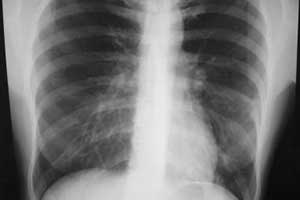

Пневмония – острое инфекционное заболевание, преимущественно бактериальной этиологии, характеризующееся очаговым поражением респираторных отделов лёгких с обязательным наличием внутриальвеолярной экссудации.

Пневмония и в XXI столетии остается важной медико-социальной проблемой. Это обусловлено, в первую очередь, ее значительной распространенностью, достаточно высокой смертностью, а также значительными экономическими потерями.

Возбудители атипичных пневмоний – микоплазмы, легионеллы, хламидии – играют заметную роль в инфекционной патологии человека.